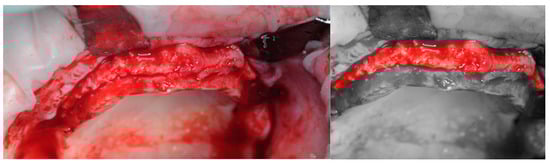

2.2. Surgery

2.3. Re-Entry Surgery